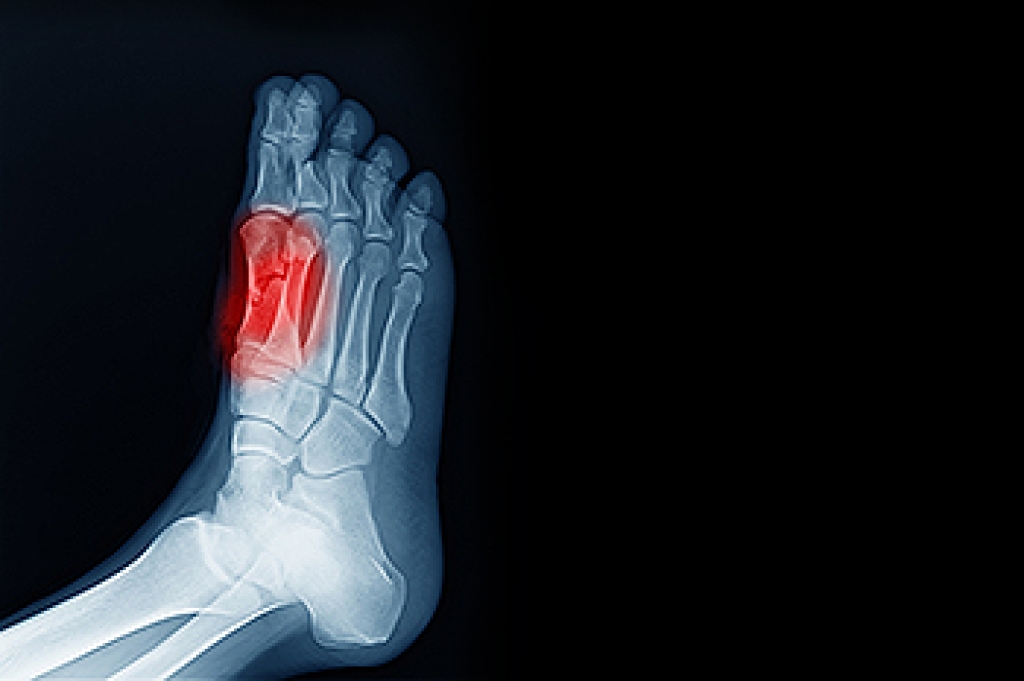

Ankle injuries, a common woe for sports enthusiasts, often leave you wondering: Is it a sprain or a break? Understanding the nuances is imperative for effective treatment. A sprain occurs when ligaments, which are the connectors between bones and joints, are forcefully stretched beyond their normal range. Notably, ankle sprains take the lead as the most prevalent sports injury. Conversely, a fracture entails a break in a bone, with a broken ankle indicating damage to tibia and fibula in the leg or calcaneus and talus bones of the foot. Fractures cause sudden pain and noticeable swelling, whereas stress fractures, smaller cracks in the bone, bring intense pain with less swelling. When uncertainty looms, seeking medical guidance is paramount. Consult a podiatrist if you suspect a fracture or ruptured ligament. Tenderness over a bone and an irregular shape of the leg or joint may signify a break or dislocation, necessitating immediate attention. An accurate diagnosis ensures the right intervention, whether it is rest and rehabilitation for a sprain or more intensive measures for a fracture. If you have sustained a serious ankle injury, be it a sprain or a fracture, it is suggested that you schedule an appointment with a podiatrist.